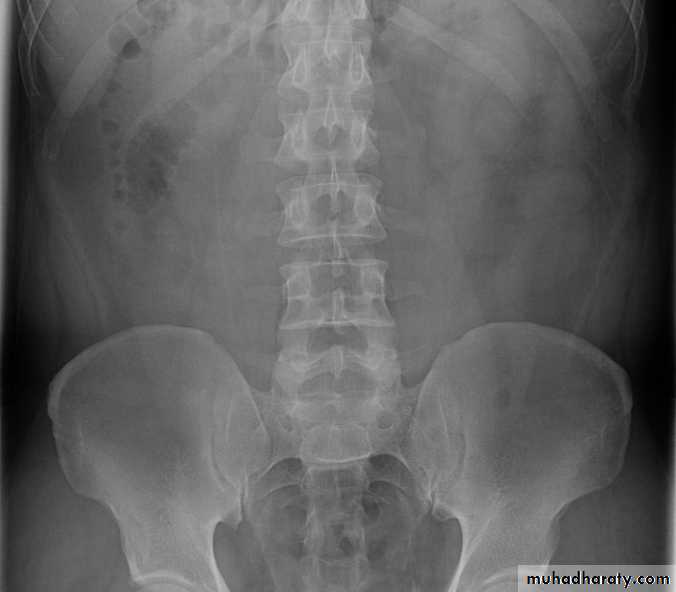

Ddx of stone on KUB :

1. Gall stone2. Calcified LN , cartilage ,fibroid,

3. Phlebolith: round, lucent centre.